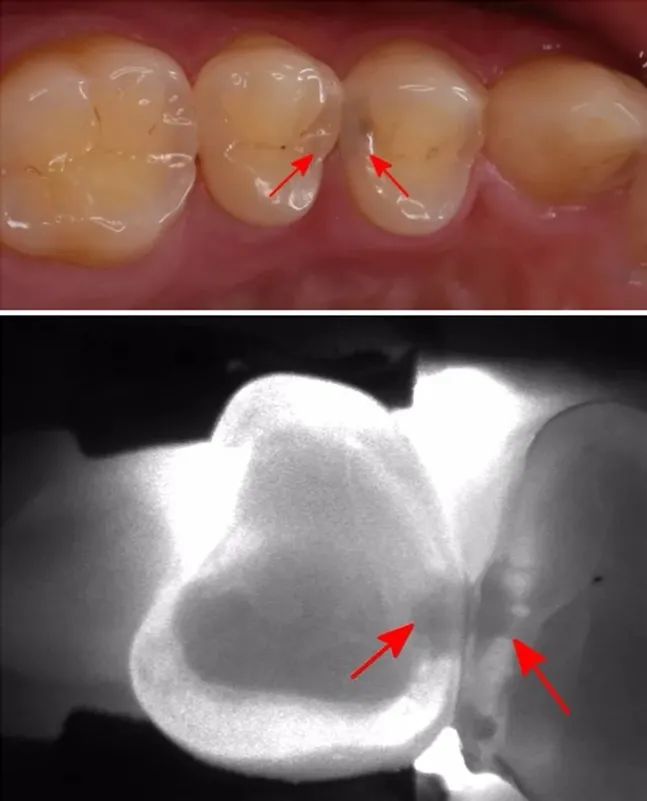

因为,有些龋齿用肉眼并不能直接观察到,它们不存在于表面,而是隐藏在深处。初期一般没有明显症状,常常难以被注意到;等到为人所察觉时,往往就已经烂得有些深了。若得不到及时治疗,最终会形成牙髓炎或根尖周病,进而影响生活质量。对付这种隐蔽的口腔健康威胁,最有效的办法就是定期进行口腔检查。

龋齿的发展是一个由浅至深的过程。起初牙齿会有点变色,出现一些小黑点和小黑线。此时已经发生了浅龋,需要做药物治疗或充填治疗。